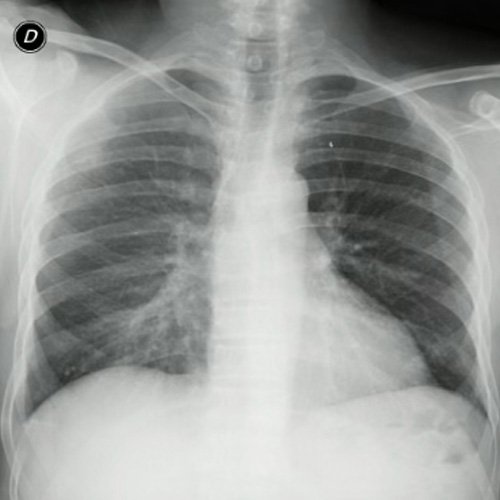

• Radiografía de tórax frente/perfil (día 3): rotada, índice cardiotorácico conservado, senos costofrénicos libres. Radiopacidad parahiliar derecha.

Radiografía de tórax frente y perfil. (día 3).